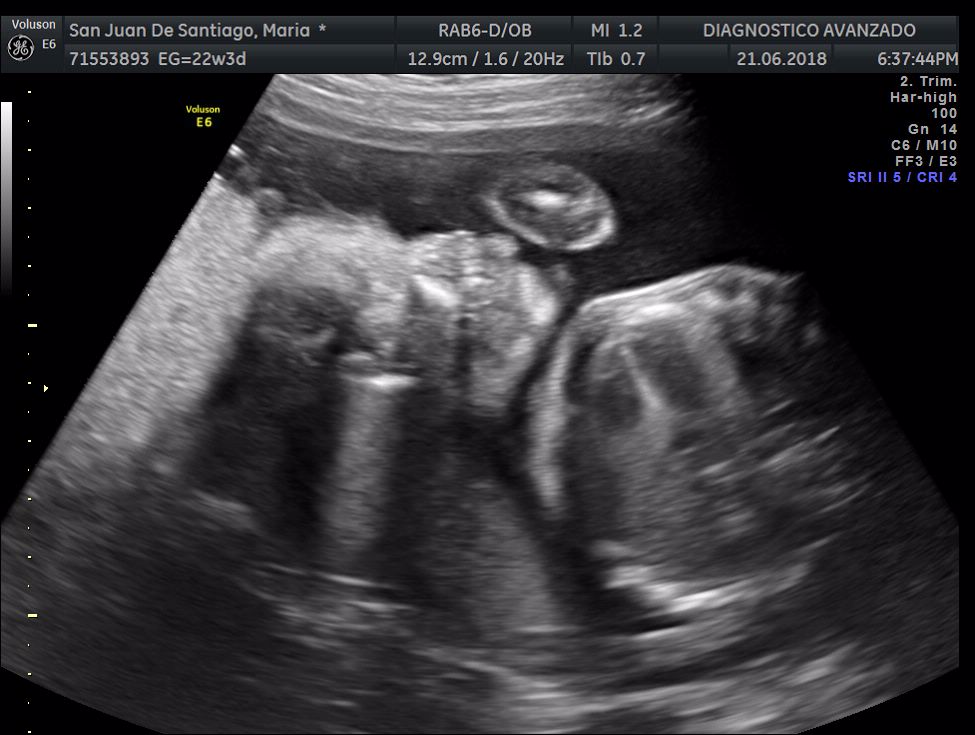

¡Hola a todos! Hoy hemos ido a hacer la tradicional ecografía 3D de la niña, os dejamos todo el material (aunque es un poco demasiado).